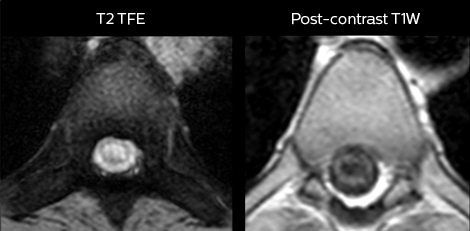

Cervical spine routine exam

This patient presented with headache that was worse with neck flexion and we see a Chiari 1 malformation with low-lying cerebellar tonsils as well as some degenerative cervical thrombolytic change.